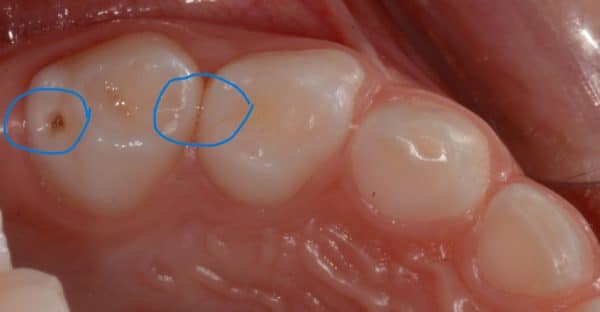

Caries dentaires affectant deux molaires de lait

Caries dentaires affectant deux molaires de lait. Elles peuvent être cachées entre les dents, non détectables lors de l’examen de dépistage. Une petite radiographie intra-orale révélera l’existence de ces caries et évitera leurs progression souvent assez rapide.